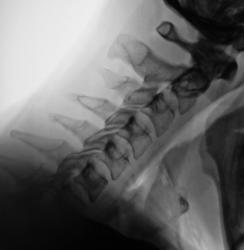

На рентгенограммах стато-функциональные изменения в шейном отделе выражены не отчетливо, можно описать как патологию, но можно описать и как норму, а вот увеличение ширины ключично-акромиального сочленения есть, возможно имеет место быть старый разрыв связок ключично-акромиального сочленения.